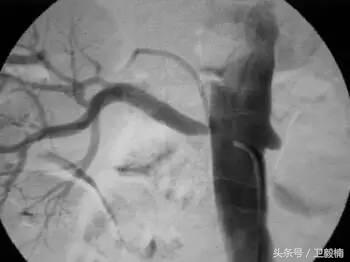

3、经皮腔内血管成形术(Percutaneous transluminal angioplasty,PTA)

60年*开代**始应用于动脉,使狭窄的血管扩张,70年代研制双腔气囊导管成功后,得到广泛应用,多用于髂、股、腘动脉及肾动脉。肾动脉PTA(或PTPA)多用于肾源性高血压,使狭窄肾动脉扩张,从而降低血压。PTA亦可用于冠状动脉,称为经皮腔内冠状动脉成形术(Percutaneous transluminal coronary angioplasty,PTCA),使硬化的冠状动扩张,以达到治疗冠心病的目的。PTA使用的导管为带胶囊的双腔导管,将胶囊段置于狭窄血管处,囊内注入含有造影剂的液体,加压至3~6个大气压,每次持续10—15o。加压可重复3~4次,多数能使狭窄血管达到扩张的效果。

PTA多用于动脉粥样硬化性狭窄的血管,其机理是粥样斑块受压,内膜和中层撕裂、伸展,使管腔增宽。其他原因的血管狭窄,如多发性大动脉炎,先天性血管狭窄,有时也可用PTA治疗。